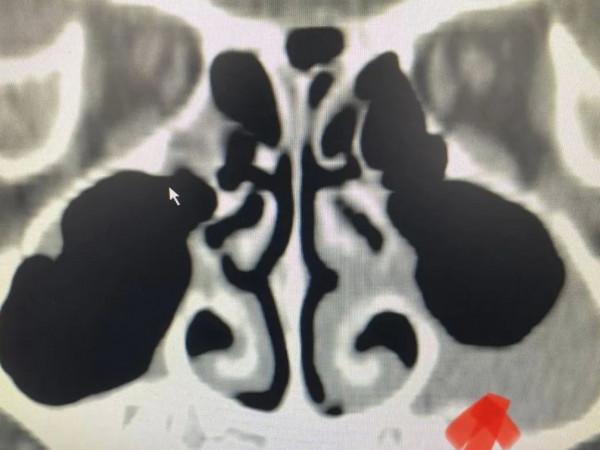

這個男孩左側上頜竇粘膜增厚明顯,鼻甲粘膜肥厚。

既有慢性鼻竇炎的臨床症狀,又有鼻竇粘膜病變,確診慢性鼻竇炎。